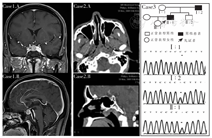

注:Case1-A、B分别为STSH-oma垂体MRI冠状位和矢状位,箭头所指为病灶; Case2-A、B分别为ETSH-oma鼻咽顶部CT横轴位和矢状位;Case3为SRTH患者家系图及其正常个体与患者基因测序图;TSH:促甲状腺激素;甲亢:甲状腺功能亢进症;STSH-oma:原位TSH分泌重体瘤;ETSH-oma:异位TSH分泌垂体瘤;SRTH:甲状腺激素抵抗综合征

病例1:原位TSH分泌垂体瘤(TSH-secreting pituitary adenomas in situ, STSH-oma),男,61岁。因多汗、心悸、体力困乏3年余,于2018年7月26日就诊山东大学附属威海市立医院。首诊检查:血清FT3>30(正常3.5~6.5) pmol/L,FT4 71.22(正常9~19.04)pmol/L, TSH 0.121(正常0.49~4.91) mIU/L,诊断为甲亢,始用甲巯咪唑10 mg,tid,po治疗。初始治疗3个月后,FT3、FT4降至正常,TSH 3.213 mIU/L。但在药物规律减量过程中出现甲状腺激素水平再度升高。患者抱怨其治疗效果不如周围其他甲亢患者。笔者发现患者在2015—2018年几乎每月1次共43次的甲状腺功能检查数据中,在高甲状腺激素状态下TSH均未得到充分抑制,多数呈现正常或增高。即使在甲状腺激素水平严重升高时依然如此。而在依次分布于4年中的5次前后间隔均为5~7个月的血清FT3和FT4均正常的甲状腺功能数据中,对应的血清TSH测定值依次为3.21、8.06、8.49、10.57和13.09 mIU/L,即在抗甲状腺药物使FT3和FT4降至正常时,随时间推移,TSH呈现进行性升高。病后无鼻塞、头疼及突眼,视力正常。家族中无甲亢患者。查体:脉搏89次/min,血压140/88 mmHg(1 mmHg=0.133 kPa)。体型消瘦,皮肤多汗。无突眼,甲状腺无明显肿大。双肺正常,心率89次/min,节律整齐,无杂音。腹部及四肢未见异常。血常规、肝、肾功能、电解质及血脂正常。甲状腺功能及相关抗体:FT3 12.47 pmol/L、FT4 35.35 pmol/L、TSH 4.676 mIU/L,促甲状腺激素受体抗体(TRAb)、甲状腺过氧化物酶抗体(TPOAb)正常;性激素6项及促肾上腺皮质激素(ACTH)正常。神经元特异性烯醇化物(NSE)16.8(正常0~17) μg/L。生长抑素抑制试验:24 h抑制率为80.67%。门诊鼻内窥镜检查:鼻咽部未见异常;甲状腺超声:甲状腺大小及形态正常,右叶下极背侧可见7.5 cm×8.3 cm×5.9 cm与6.5 cm×6.3 cm×5.1 mm两个等回声结节,边界清晰,形态规则。垂体MRI:鞍区占位,见图1中Case1-A和Case1-B。术前诊断:原位TSH分泌垂体瘤。患者于术前采用奥曲肽100 μg, q 8 h,ih进行术前准备,术前TSH降至0.663 mIU/L,FT3 9.14 pmol/L,FT429.59 pmol/L。手术采用经鼻蝶垂体瘤切除术。瘤体病理组织学发现:肿瘤体积2.0 cm×2.0 cm×1.5 cm,组织呈灰红色,细胞丰富,增生活跃。免疫组化显示:TSH(+)、催乳素部分(+)、ACTH(-)、P53(<25+)、Ki(3%+)。术后次日TSH正常(0.663 mIU/L),FT3 11.53 pmol/L,FT4 44.88 pmol/L,仍处较高水平。术后11日FT3、FT4降至正常,TSH 0.093 mIU/L。术后5个月随访:TSH 0.708 mIU/L,FT3 4.80 pmol/L,FT4 18.15 pmol/L,完全正常。诊断:STSH-oma。

病例2:异位TSH分泌垂体瘤(ectopic TSH-secreting pituitary adenoma,ETSH-oma),男,41岁。因多汗、心悸、消瘦两个月于半年前就诊于当地医院,体检发现有心房纤颤。甲状腺功能检测:血清FT3 24.08(2.8~7.1)pmol/L、FT4 75.73(12~22) pmol/L、TSH 7.26 (0.27~4.20) mIU/L,诊断为甲亢伴发心房纤颤。给予丙基硫氧嘧啶300 mg/d持续强化治疗,并口服心得安或心律平,1个月后心脏转为窦性心律,半年后FT3 11.54 pmol/L、FT4 27.09 pmol/L、TSH 14.08 mIU/L。提示甲状腺激素水平并未恢复正常,且TSH进一步升高。2009年9月转诊山东大学附属威海市立医院。患者无突眼,甲状腺Ⅱ°肿大,触诊无结节感,质地中等。肺部正常,心率100次/min,心音强弱不等,心律绝对不齐。腹部检查未见异常。肢体近端肌群无萎缩,双手平举轻度震颤。实验室检查:FT3 14.30 pmol/L、FT4 29.86 pmol/L、TSH 5.72 mIU/L;甲状腺球蛋白抗体(TGAb)<30%,甲状腺微粒体抗体(TMAb)<15%,生长激素0.7(<5.0) μg/L,催乳素14.9(4.1~18.4) μg/L,NSE 22.31(<16.3 μg/L)。善宁抑制试验提示:TSH可被抑制到基础值的30.8%,促甲状腺激素释放激素(TRH)兴奋试验:TSH不被兴奋(TSH较基础值增加<2 mIU/L)(TRH由上海利珠东丰生物科技有限公司提供)。垂体MRI平扫蝶鞍区未见异常。头颅CT见于鼻咽顶部正中可见一分叶状软组织密度影,向鼻咽部气道突出,病灶呈不均匀强化,最大横截面积约1.9 cm×1.7 cm,边界清楚,见图1中Case2-A和Case2-B。ECT显示甲状腺摄锝功能增强。综合分析考虑异位TSH分泌垂体瘤。2009年11月20日以"鼻咽部肿物(可疑异位TSH分泌瘤?)"在威海市立医院耳鼻喉科行鼻中隔及鼻咽部区域肿物切除术。病理报告:鼻咽顶部垂体腺瘤,浸润性,累及骨组织。镜检:瘤组织位于鼻黏膜(假复层柱状纤毛上皮)下,无包膜,组织内肿瘤细胞弥漫分布,在黏膜及纤维组织间浸润性生长,瘤组织呈弥漫实性团块及窦隙状排列。细胞形态不规则,多数呈圆形、多角形,部分呈梭形,胞浆较丰富,并见微细颗粒,有的胞浆透明,核圆形及卵圆形,部分偏位,染色质纤细,可见核仁。肿瘤细胞免疫组化示:TSH(+)、生长激素弱(+)。电镜检查:细胞胞质内可见散在分布电子致密颗粒,颗粒直径约0.1~0.2 μm,圆形,无被膜,局部成簇分布。患者术前甲状腺功能FT3 16.07 pmol/L,FT4 30.28 pmol/L,TSH 6.39 mIU/L。术后次日FT3 4.85 pmol/L,FT4 13.54 pmol/L,TSH 1.86 mIU/L,甲状腺激素和TSH浓度均恢复正常。随访9年未见复发。

病例3:甲状腺激素抵抗综合征(thyroid hormone resistance syndrome,RTH),男,47岁,甲状腺肿大伴心悸、多汗与乏力7年就诊山东大学附属威海市立医院,7年前曾因心房纤颤和心绞痛于当地医院检查发现患有高脂血症,冠状动脉CT显示前降支重度狭窄而给予冠状动脉支架植入术。术后心绞痛缓解,心房纤颤持续。转诊北京阜外医院发现患者血清FT3、FT4严重升高,证实存在甲亢。始用甲巯咪唑治疗,持续治疗1年余,病情依旧时轻时重,反复无常。尤其在活动及饮酒后症状明显加重。自诉每在服用甲巯咪唑后,TSH水平升高明显,多次复查FT3、FT4,均处升高状态,甲巯脒唑足量强化治疗也很难降至正常。平时无怕冷和便秘症状。患者自幼注意力不易集中,计算力低下、数学成绩较差。家族史:其父身材偏矮小(身高155 cm),自诉容易困乏,反应相对迟缓,上学数学成绩差。患者身高:168 cm,体重74 kg,体重指数:26.21 kg/m2。血压125/82 mmHg,眼球无突出,甲状腺Ⅱ°肿大,质软,无结节感,甲状腺血管杂音(—),双肺正常,心率90次/min,节律不齐,心音强弱不一,无杂音。腹检正常。双手无震颤,下肢无水肿。实验室检查:谷草转氨酶35.2(正常0~33)U/L、血尿酸481(正常102~416)μmol/L、甘油三酯3.35 (0~2.30)mmol/L、总胆固醇6.49(正常3.10~5.20)mmol/L、NSE 6.0(正常<16.3) μg/L、催乳素6.00(正常5.18~26.53)μg/L、生长激素2.35(0.16~26.00)mIU/L。生长抑素抑制试验:被抑制率为54.34%。甲状腺超声:双侧甲状腺体积增大,形态饱满,无结节,血流正常。甲状腺99mTc-O4显像:摄锝功能增强。头颅CT(平扫+增强):鼻咽部和垂体未见占位性病变未见异常。因心脏支架未做垂体MRI检查。心脏彩超示节段性的室壁运动异常、左房增大、二尖瓣少量返流、心率失常。双耳电测听:正常。家族成员筛查:父亲FT3、FT4轻中度增高,TSH 1.58 mIU/L。患者及其亲属基因检测发现其本人与父亲均为甲状腺激素受体(TR)β基因第10外显子的第453位密码子存在点突变(杂合子突变),密码子由CCT突变为ACT,编码的氨基酸由脯氨酸变为苏氨酸(P453T),见图1中Case-3。